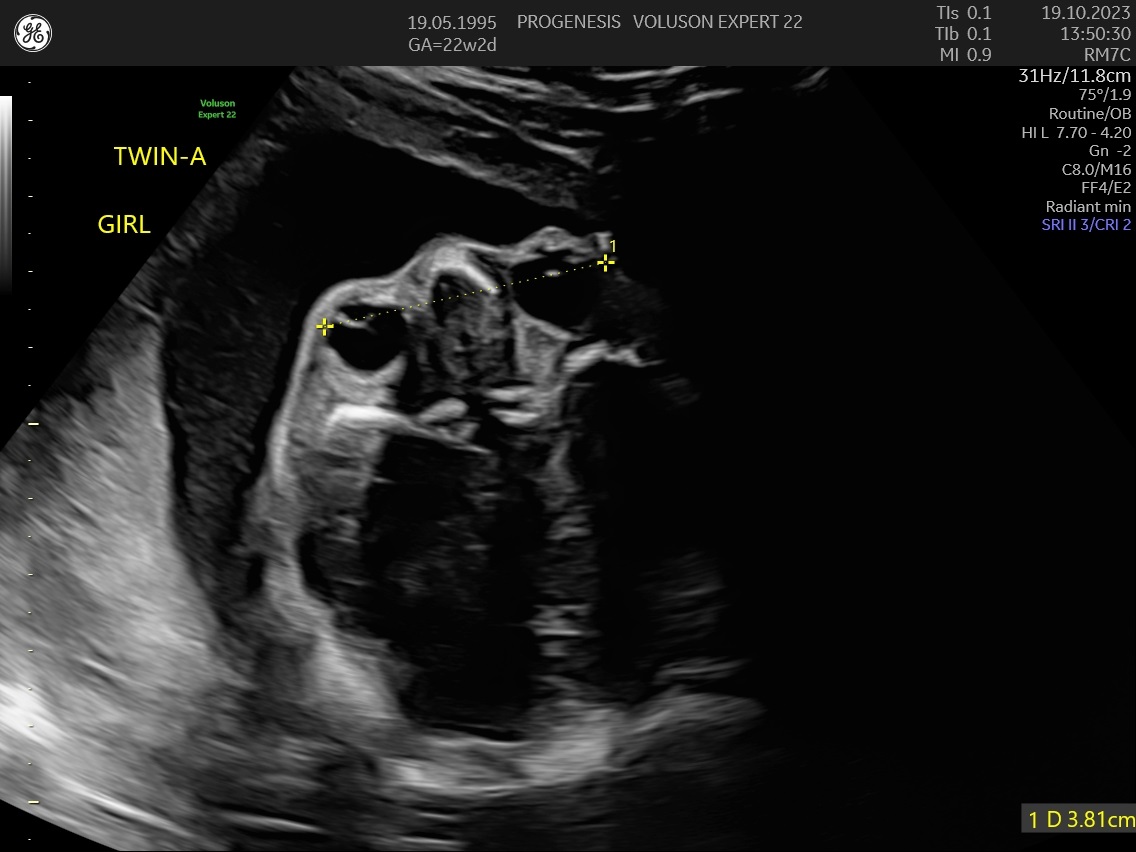

Υπερηχογράφημα Β΄Επιπέδου (20-24 εβδομάδων)

α) Η λεπτομερής αξιολόγηση της εμβρυϊκής ανατομίας, όπου αναγνωρίζονται τυχόν ανατομικές ανωμαλίες.

γ) Ο έλεγχος της ανάπτυξης του εμβρύου, του πλακούντα, του ομφαλίου λώρου και του αμνιακού υγρού.